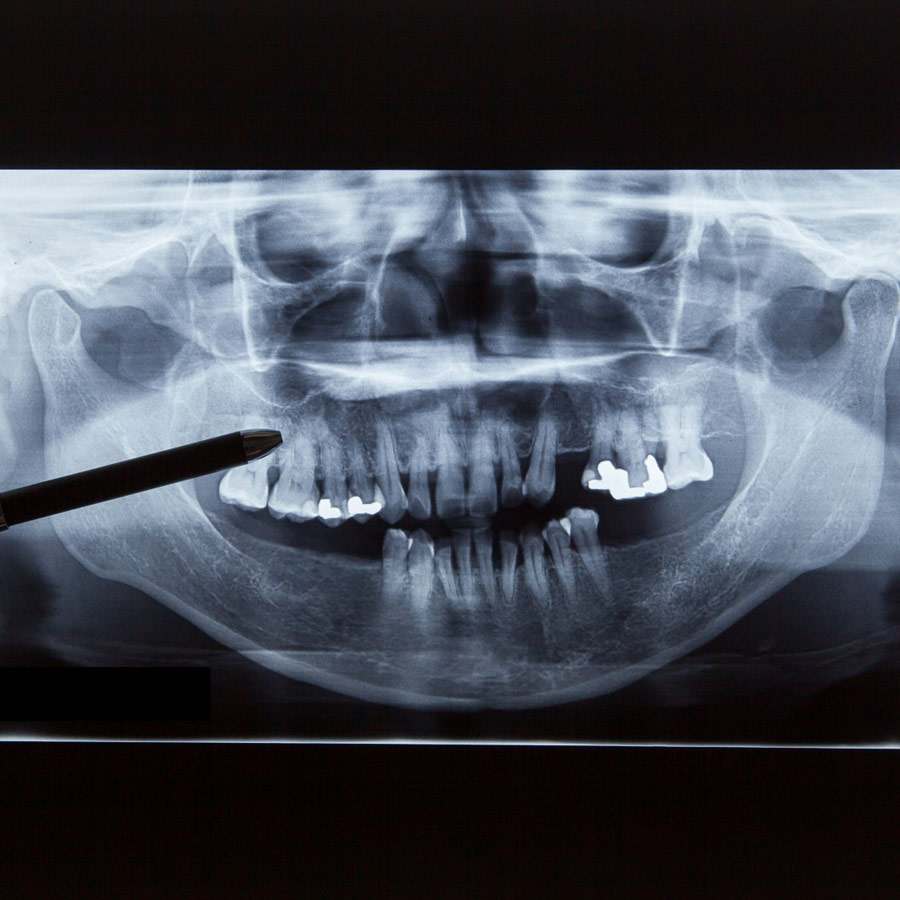

يتميز جهازنا ثلاثي الأبعاد بدقته الفائقة، حيث يُقدم صورًا بانورامية فائقة الوضوح للفم والأسنان، ويُساعدنا على تشخيص أي مشاكل أو أمراض في الفم والأسنان بدقة عالية، ويتميز أيضًا بسعته حيث يستغرق عدة ثوانٍ فقط لتصوير التشريح الكامل للفم والأسنان.